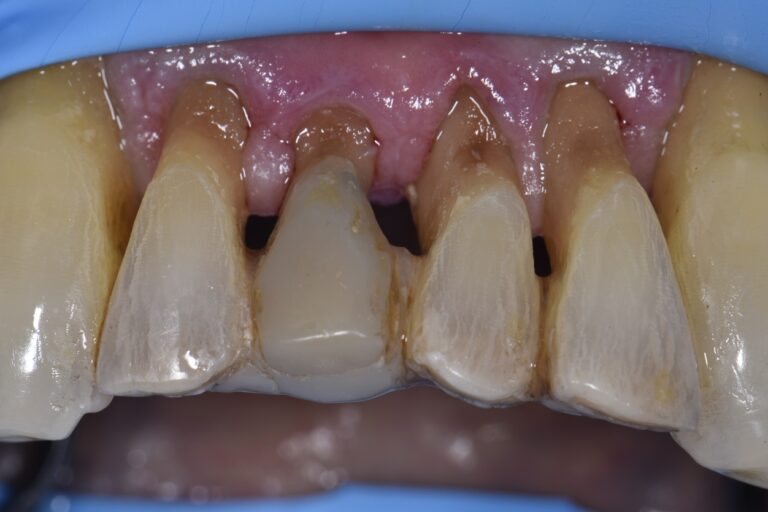

Cervical Abrasion Lesions Restored with GC Essentia U

Cervical Abrasion Lesions Restored with GC Essentia U What Is Denture Abrasion dentures (artificial teeth) are synthetic replacements for missing natural teeth. this condition, called dental abrasion, can occur when any foreign object causes friction against your teeth and gradually wears away the enamel on the surface. Some dentures replace a few missing teeth. what is dental abrasion? dental abrasion refers to the wearing away of tooth enamel,. What Is Denture Abrasion.